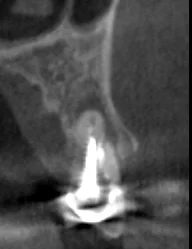

Давайте сравним снимки зубов, сделанные при помощи визиографа (слева), и при помощи компьютерной томографии (справа).

Как говорится, ощутите разницу. КТ - гораздо более точная и своевременная диагностика.

Воссоздавая орган (зуб) или даже совокупность органов, необходимо предельно точно знать исходную ситуацию. Корни зубов, каналы зубов, крупные сосудисто-нервные пучки, идущие внутри костной ткани, верхнечелюстная пазуха во всех подробностях и т.д. - в неискаженном виде все это можно увидеть только на компьютерной томограмме. Стоит ли говорить, что все эти структуры важны для имплантации, так как могут быть легко поврежденфы в ходе операции.

Как получить гарантированный результат имплантации? При помощи компьютерной томографии!